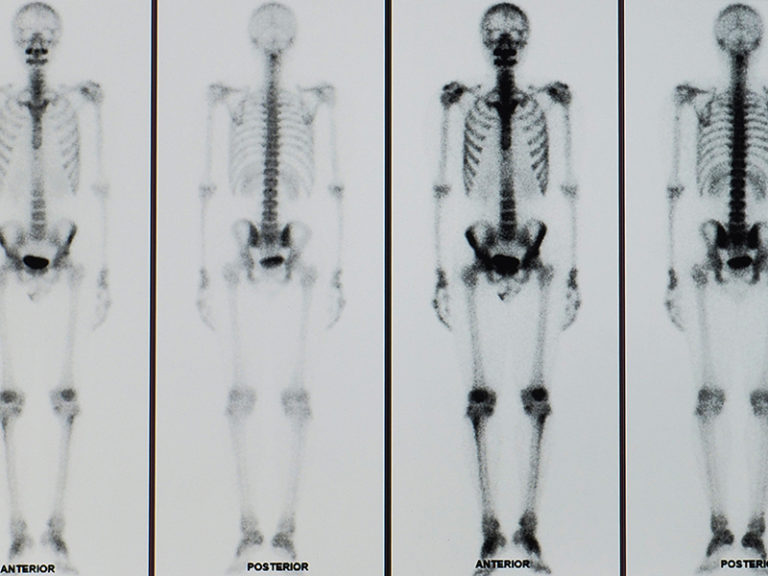

Tutto quello che c'è da sapere sulla Scintigrafia ossea Rivista La Salute